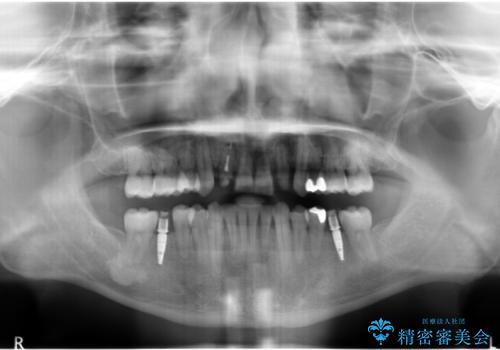

下の歯がないところに、奥歯が倒れこんでいたため、矯正治療で倒れこんだ歯を起こして、インプラントを植立しました。

- 197万円 (矯正治療95万円、インプラント治療72万円(下顎両側6)、その他補綴治療30万円(上顎両側2))費用は治療当時の料金となります

上顎の小臼歯2本、下顎の親知らずを抜歯しています。